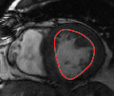

V-B Ventricle Segmentation: Comparison of Three Registration Schemes

In this experiment, we focus on real cardiac MRI data and compare registration methods used for segmentation of the LV and RV. We visually compare the tracking results given by our method to (M1) registration of only the interior of current estimate of the ventricle to a subset of next image (to show whole image registration is needed), and to (M2) standard full image registration with global smoothness. M1 is achieved by computing just the inside velocity with Neumann boundary conditions on (normal constraint does not apply in M1). The best results with respect to ground truth are chosen by choosing the optimal parameter in all methods. Results on LV and RV tracking for a full cardiac cycle are given in Figure 6 for the LV and Figure 7 for the RV. Registering only the organ (M1) results in errors (as the background registration is helpful in restricting undesirable registrations of the foreground). Globally smooth registration (M2) smooths motion from irrelevant background structures into the ventricles, which results in drifting from the desired boundary. Our method, which smooths within regions with satisfying the physical constraint, is able to achieve the most accurate results.